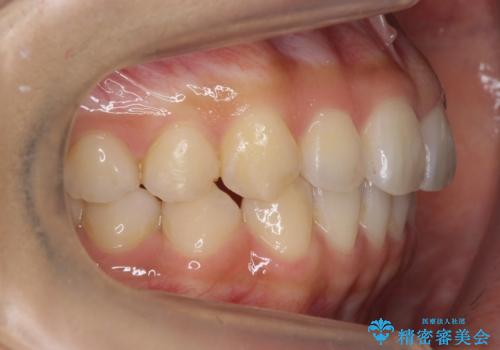

- 1年7ヶ月

インビザラインで歯を抜かずに並べました。

初回:上顎16ステージ 下顎22ステージ

リファインメント: 上顎23ステージ 下顎20ステージ